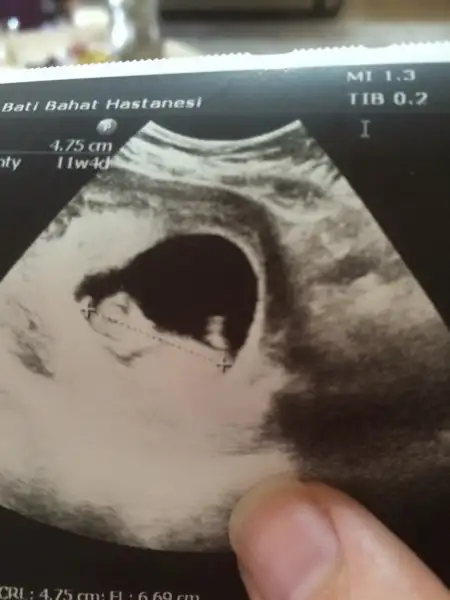

totosunu havaya diktiğine göre erkek derler...hayırlısı olsun canım maşallahh

Ooof Sunrise sen de mi? Kim görse aynısını söylüyor. Şu kese teorisine de atmıştım daha önce orada da erkek demişlerdi. Biz daha çok kız istiyoruz vallahi ne yalan söyleyeyim. Hattâ kızı gördüğüm gün gelip burada bilemediniz işte diye Suzan Avcı kahkahaları atacağım. Ahdettim resmen.

Bütün batıllar erkek diyor benimde çin takvimi rus takvimi alyans testi bakalım doğruluğunu görecez

Bence bu erkek işte. Erkek dediğin poposunu havaya dikmez zilli gibi hem.